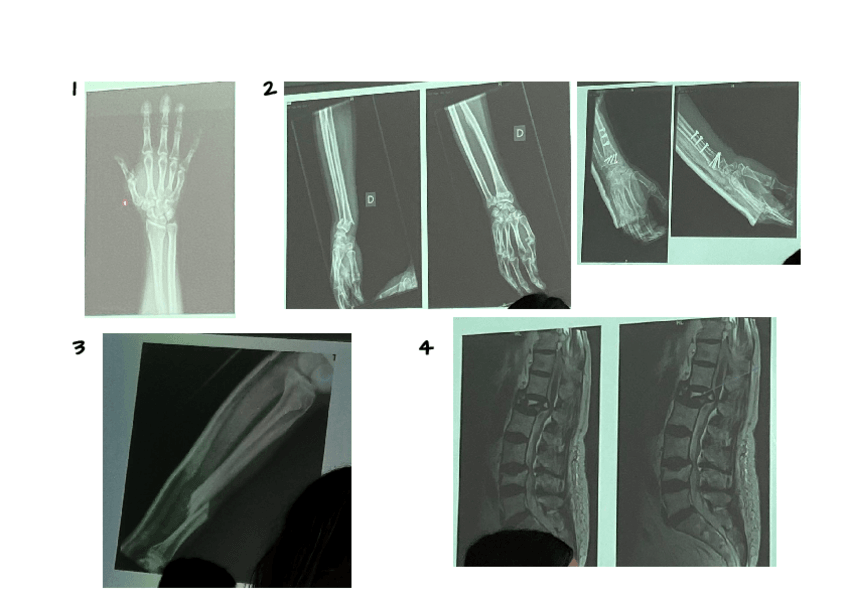

He publicado nuevos apuntes de 2º Cuidados de Enfermería en Procesos Osteoarticulares: RXS-TRAUMA.pdf

14 páginas